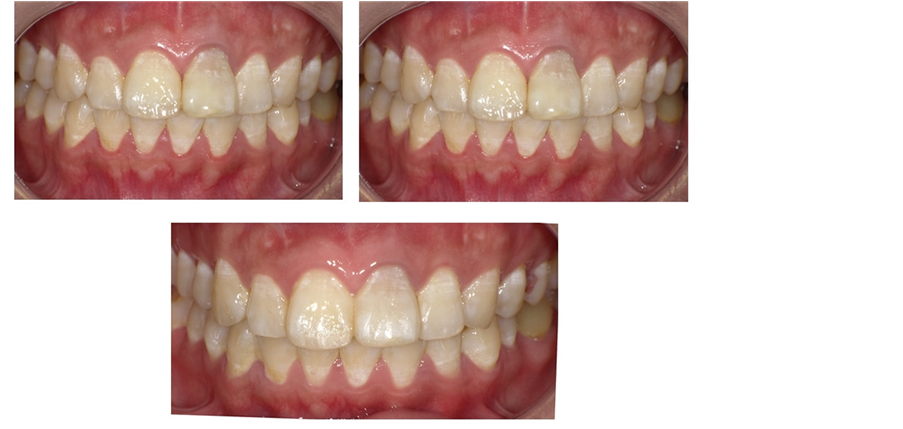

A 28-year-old female patient was treated in Department of Stomatology, Fujian Medical University Union Hospital on March 11th 2016 with chief complaint of “gingiva of the left upper anterior tooth suppurated for one month”. A decade ago, the patient had tooth trauma. One year ago, the patient had root canal therapy in other hospital for the 21st tooth. One month ago, the patient was treated in our hospital for repeated suppuration at gingiva of the 21st tooth. The patient is healthy in the past, denying systematic disease, infectious disease, drug allergy history, poisoning history and trauma history in last ten years. Clinical para-oral examination (Figures 1-2): The maxillofacial region is basically symmetrical in left and right; no tenderness in temporal-mandibular joint and no click and fricative when opening and closing mouth; parotid gland is normal in palpation; no swelling in lymph gland. Intraoral examination: there is tooth stain and fistula at gingiva in the 21st tooth, the crown is dark and 21 (++) is not loose, the teeth of the teeth were normal and the 11 teeth were cut by 1/3. X-ray periapical film shows (Figure 3): 21st tooth is low-density shadow under large-area and high-density projection at apex with defective root filling. The patient wanted to improve the tooth color without wearing too much tooth when solving the suppuration at apex.

mm (Figures 4-6). 3) Scratch the apex and wash it with normal saline. Restore and suture the mandibular with minocycline smeared in partial (Figure 7). 4) Post-operative CBCT shows that root filling was improved and the resistant projection of agglomerate at apex disappeared (Figures 8-9). 5) Fistula disappeared 1 week after operation (Figure 10). 6) Intracoronal bleaching was conducted and then medical prescription was changed twice in follow-up visit. The color of 21st tooth became 11 and 12 with resin repair at the incisal margin of 21st tooth. 7) The color change of bleaching opisthosoma is relatively obvious than that in neck. The color of tooth neck is dark. The protective screen was established for the third bleaching. Four days later, further consultation was conducted with color of tooth neck improved. The patient was satisfied (Figure 11). 8) 1, 3, 6 and 12 months after operation, further consultation was conducted in follow-up (Figure 12).